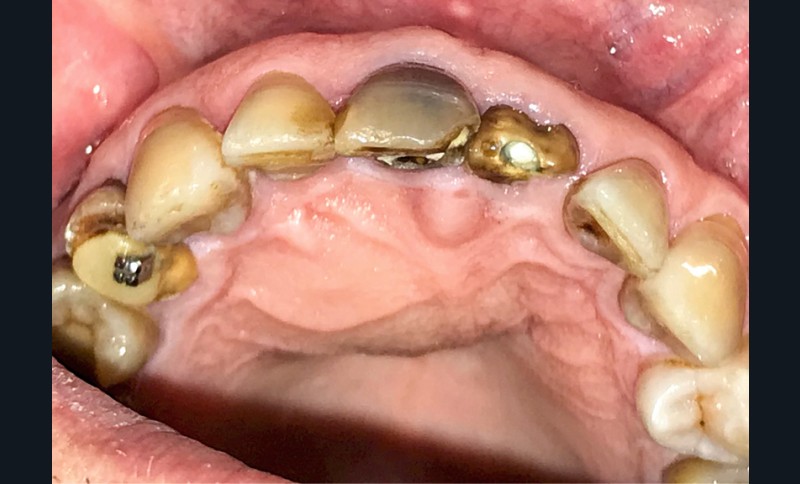

- Lorsque le kyste devient volumineux : possibilité de fenestrer la corticale palatine et/ou vestibulaire. Il peut également se développer dans les fosses nasales ou être associé à des résorptions radiculaires (moins de 25% des cas) (fig. 4).